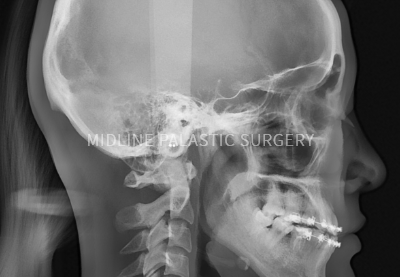

일반적인 상담으로는 확인할 수 없는 피부조직과, 코 뼈, 비중격 연골 등의 상태를 3D-CT로 촬영한 데이터를

기반으로 입체적이고 정밀하게 분석하여 보다 안전하고 아름다운 코를 완성합니다.

3D-CT를 통해

실리콘 모양, 조직의

상태, 최초 수술 방법 등 정밀 분석

CT 분석을 토대로

코 뼈의 상태를

확인하고 꼼꼼한

수술 계획 수립

수술 전 3D-CT 촬영을 통해 코뼈와 비중격의 크기, 휘어진 정도 등을

전문의와 꼼꼼히 확인 한 후 과학적으로 분석하여 부작용을 줄이며, 비중격만곡증 등 기능적인 부분까지 체크해 안전하고 정확도 높은 수술 계획을 수립합니다.